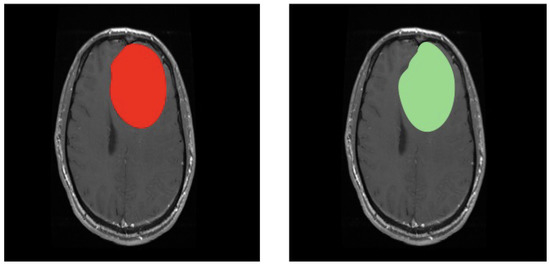

3.1. First Scenario